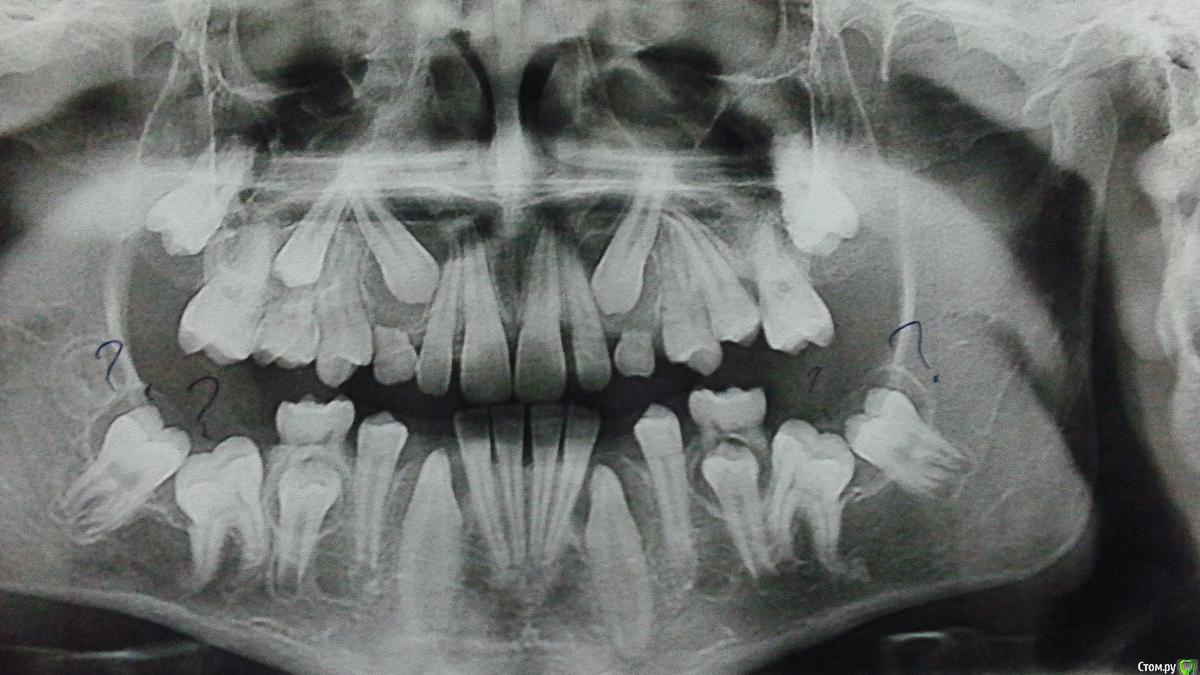

Лели Опубликовано 2 ноября, 2015 Поделиться Опубликовано 2 ноября, 2015 Уважаемые доктора! Хочу услышать Ваше мнение по поводу плана лечения этого пациента! Может у кого нибудь есть опыт ведения пациентов с такой вот ретенцией и дистопией 47, 46, 36, 37. Ребёнок мальчик 14 лет Ссылка на комментарий

Лели Опубликовано 2 ноября, 2015 Автор Поделиться Опубликовано 2 ноября, 2015 Вот фото Ссылка на комментарий

Yana guapa Опубликовано 3 ноября, 2015 Поделиться Опубликовано 3 ноября, 2015 я бы в первую очередь сделала бы КЛКТ. много нужной информации можно найти как для ортодонта, так и для хирурга. Ссылка на комментарий

Yana guapa Опубликовано 3 ноября, 2015 Поделиться Опубликовано 3 ноября, 2015 Можно разместить кейс в разделе хирургии, пусть хирурги выскажут свое мнение по поводу кист (имхо) http://i11.pixs.ru/storage/3/0/4/Snimokekra_3622406_19376304.png Ссылка на комментарий

АнтонТЛТ Опубликовано 3 ноября, 2015 Поделиться Опубликовано 3 ноября, 2015 Яна, надо было тягу не к зубам давать а к неподвижным структурам (миниимплантам или микропластинам).Кист на снимке не вижу. 2 Ссылка на комментарий

АнтонТЛТ Опубликовано 3 ноября, 2015 Поделиться Опубликовано 3 ноября, 2015 По теме, надо Кт Ссылка на комментарий

CRAZYDUCK Опубликовано 3 ноября, 2015 Поделиться Опубликовано 3 ноября, 2015 Задержка прорезывания, еще и клыков и премоляров (ну это Вы и сами видите), может подождать прорезывания нижних клыков и установить брекеты и кнопки с петелькой или мини трубки на 6 и посмотреть как они себя поведут (выйдут или нет ).дуга будет легкая и думаю ,даже если есть анкилоз ,большой деформации зубного ряда не будет. Если анкилоза 6 ых нет , то и7 легче прорезаться будет .Подождем мнения опытных коллег, интересно ...Доктора , интересует вопрос определения анкилоза . Для его определения необходимо кт , может кто- нибудь описать, как это выглядит ? Или кт тоже не 100% даст информацию о наличии или отсутствии анкилоза ? Ссылка на комментарий

Monkey Опубликовано 14 ноября, 2015 Поделиться Опубликовано 14 ноября, 2015 (изменено) Интересный кейс.Может стоит начать с удаления зачатка 48 и затем вскрыть капюшон над ретенироваными. Авось пойдут.Мне кажется или там кисты прорезывания? Изменено 14 ноября, 2015 пользователем Monkey Ссылка на комментарий